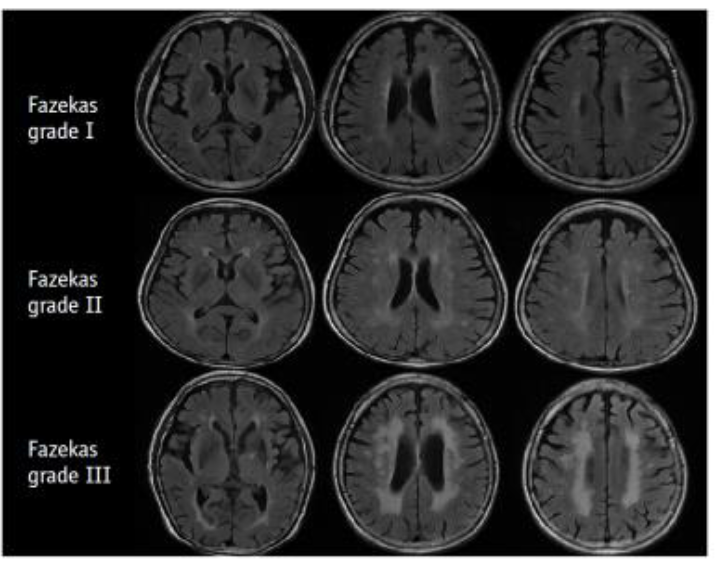

而第二種常見病因為血管性失智症,約佔30%,近期發現阿茲海默症和血管性失智症之間有重疊並存情形,又稱為混合型,而小血管疾病(圖二)可能同時是導致失智症的促進因子和病因。其他不太常見但同屬於退化性失智症,且同樣具破壞性認知功能障礙的神經退化性疾病是:路易氏體失智症 (Lewy body dementia) 約佔4.2%、額顳葉型失智症 (frontotemporal dementia)約佔2%(圖三)。

( 圖二)血管性失智症之小血管缺血病變白質斑塊分級。│AJR 1987;149:351-356